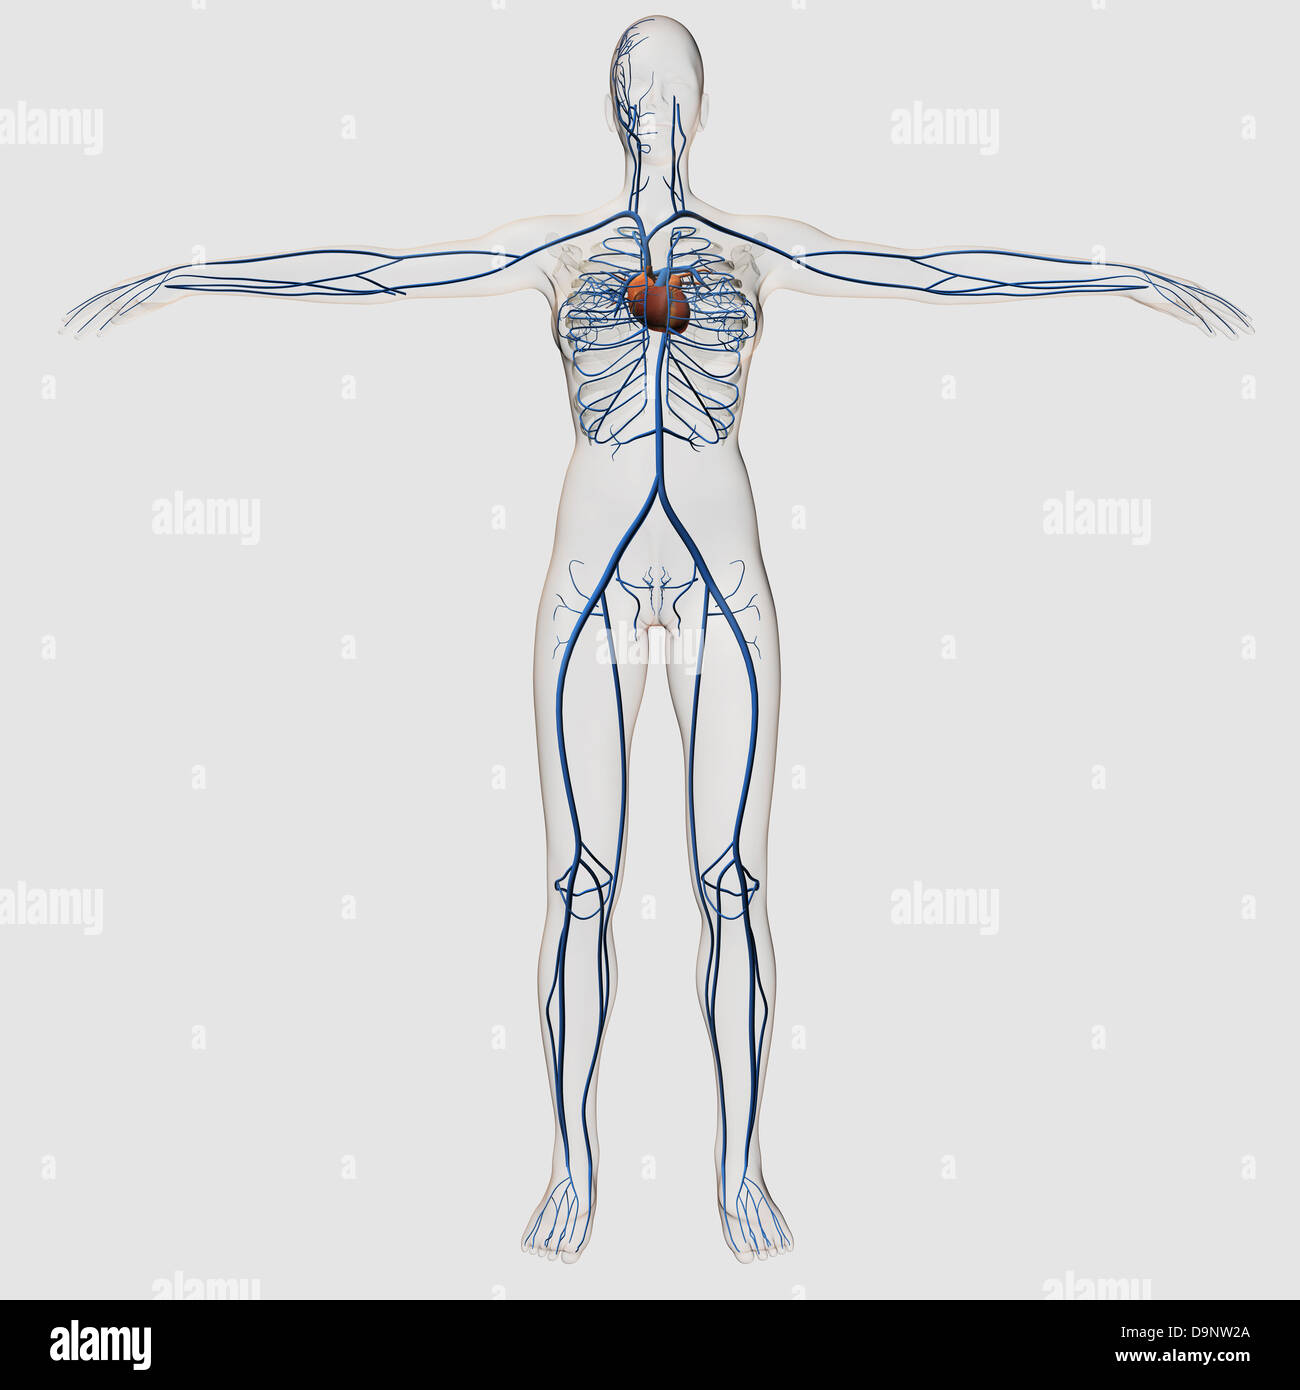

Medical illustration of female circulatory system with heart and veins visible, full body view. Stock Photohttps://www.alamy.com/image-license-details/?v=1https://www.alamy.com/stock-photo-medical-illustration-of-female-circulatory-system-with-heart-and-veins-57643666.html

Medical illustration of female circulatory system with heart and veins visible, full body view. Stock Photohttps://www.alamy.com/image-license-details/?v=1https://www.alamy.com/stock-photo-medical-illustration-of-female-circulatory-system-with-heart-and-veins-57643666.htmlRFD9NW2A–Medical illustration of female circulatory system with heart and veins visible, full body view.